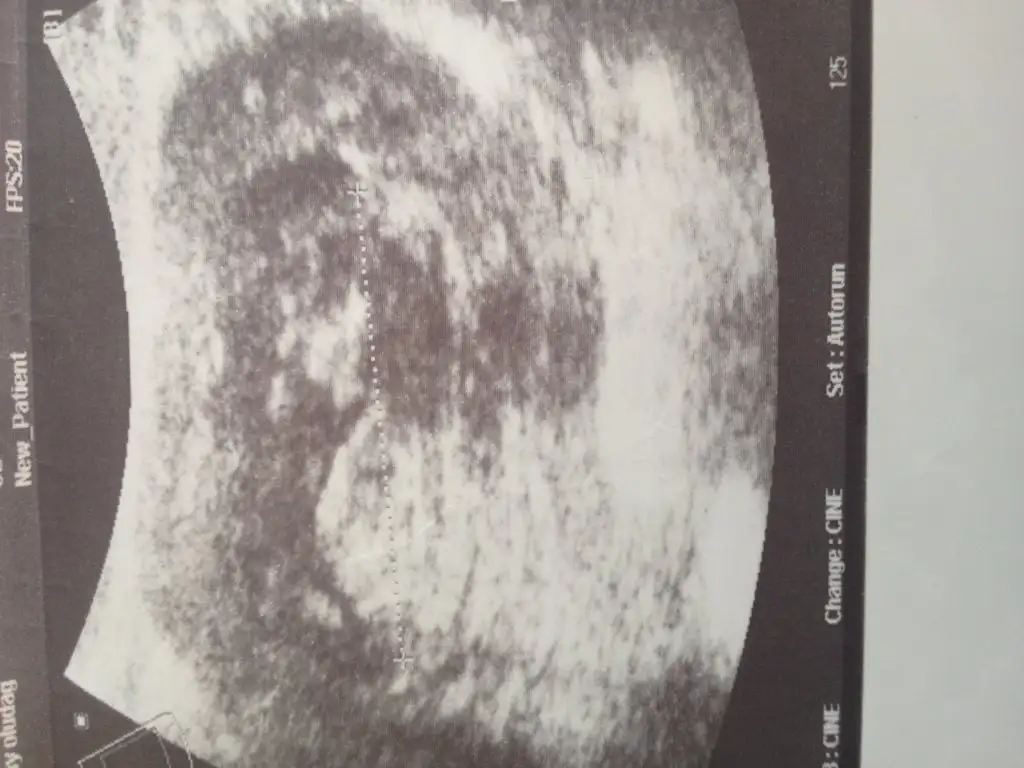

Kizlar buda arkadasimin bu sayfadan bahsedince cok merak etti bide bu resimlere yorum yaprmisiniz lütfen

Eklentiler

• image.webp

image.webp

34,7 KB · Görüntüleme: 86

30,3 KB · Görüntüleme: 95